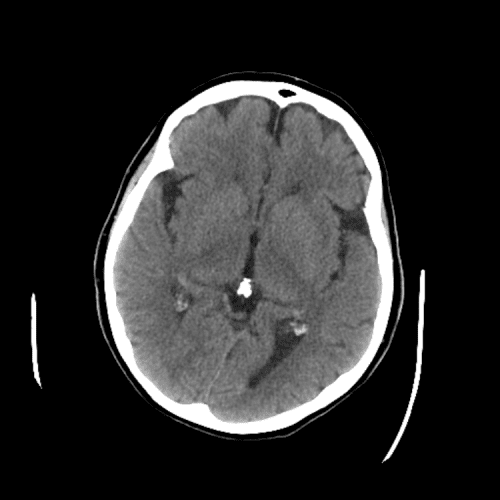

PCA infarct